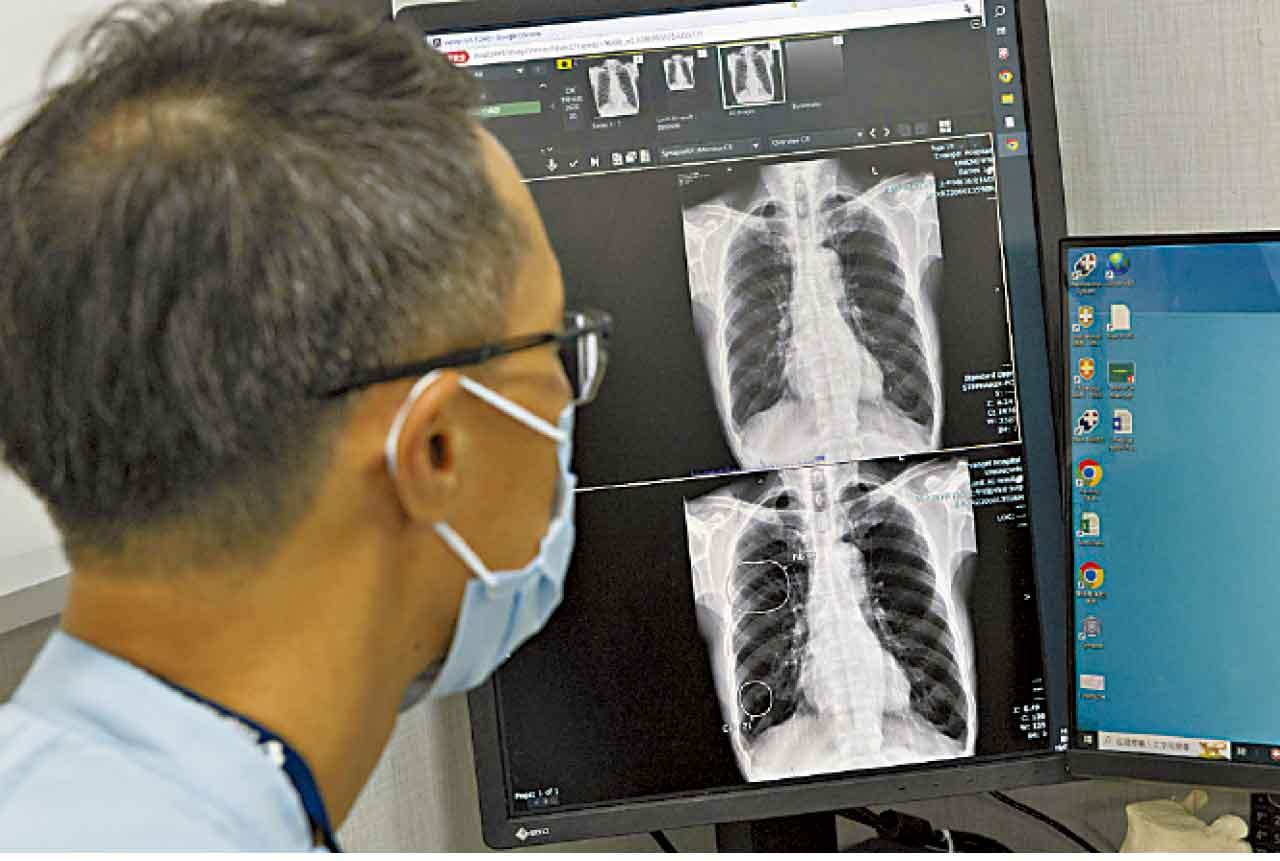

醫院放射診斷部試驗引入AI輔助處理影像,協助診斷。

播道醫院照顧病人無微不至,服務比較個人化(high touch)。但醫院亦要與時並進,借助醫療科技為病人提供針對性的體檢服務,如近年深受歡迎的骨質密度檢查(DEXA),以及判斷肝臟硬度或脂肪程度的肝纖維化掃描檢查,在儀器購置初期亦會以一個非常合宜的價錢提供服務予有需要病人。院長助理Canice補充,「最近醫院放射診斷部試驗引入AI輔助處理影像,結合高運算能力電腦與多元健康數據對照,協助放射診斷部同事更快作出初步診斷,藉此加強服務質素。」而自去年4月起,醫院又為入院部和門診部病人提供專門的傷口護理服務。她表示,手術後病人如處理傷口不當,便會影響康復過程,因此由專科護士提供傷口護理服務,是術後復康的重要一環。